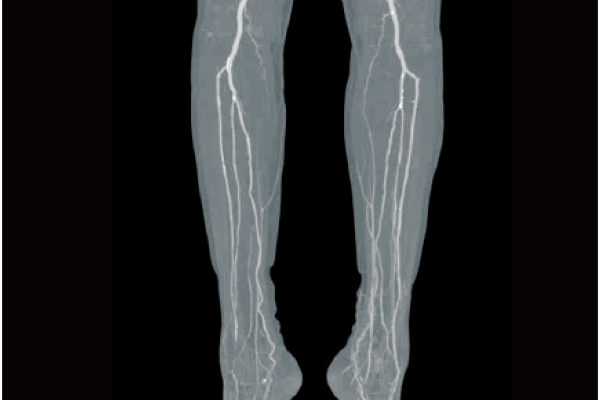

Based on the previously stored information, the areas recognized as blood vessels are extracted.

Vessels are extracted with one click by using image recognition technology.